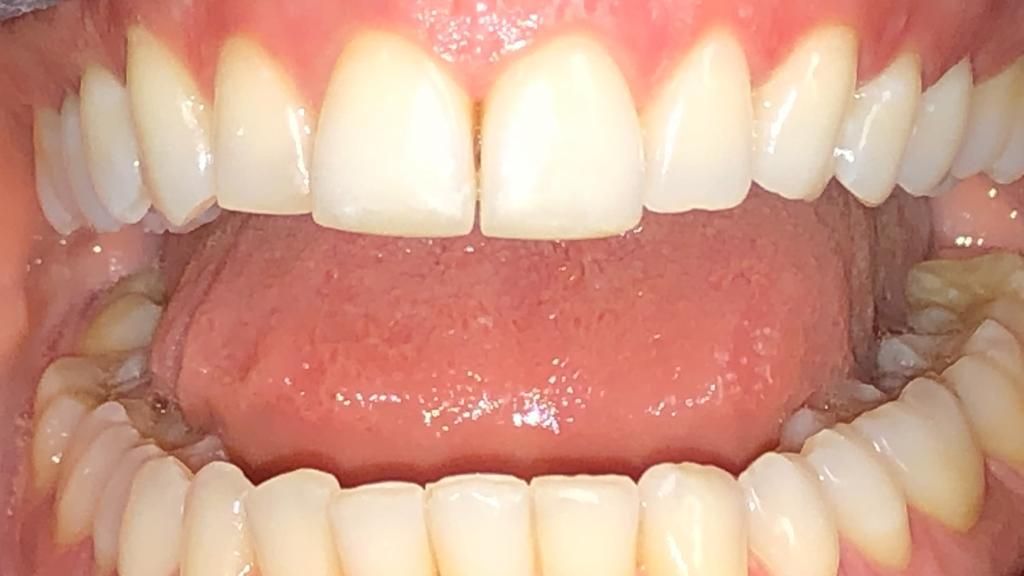

Foto e video